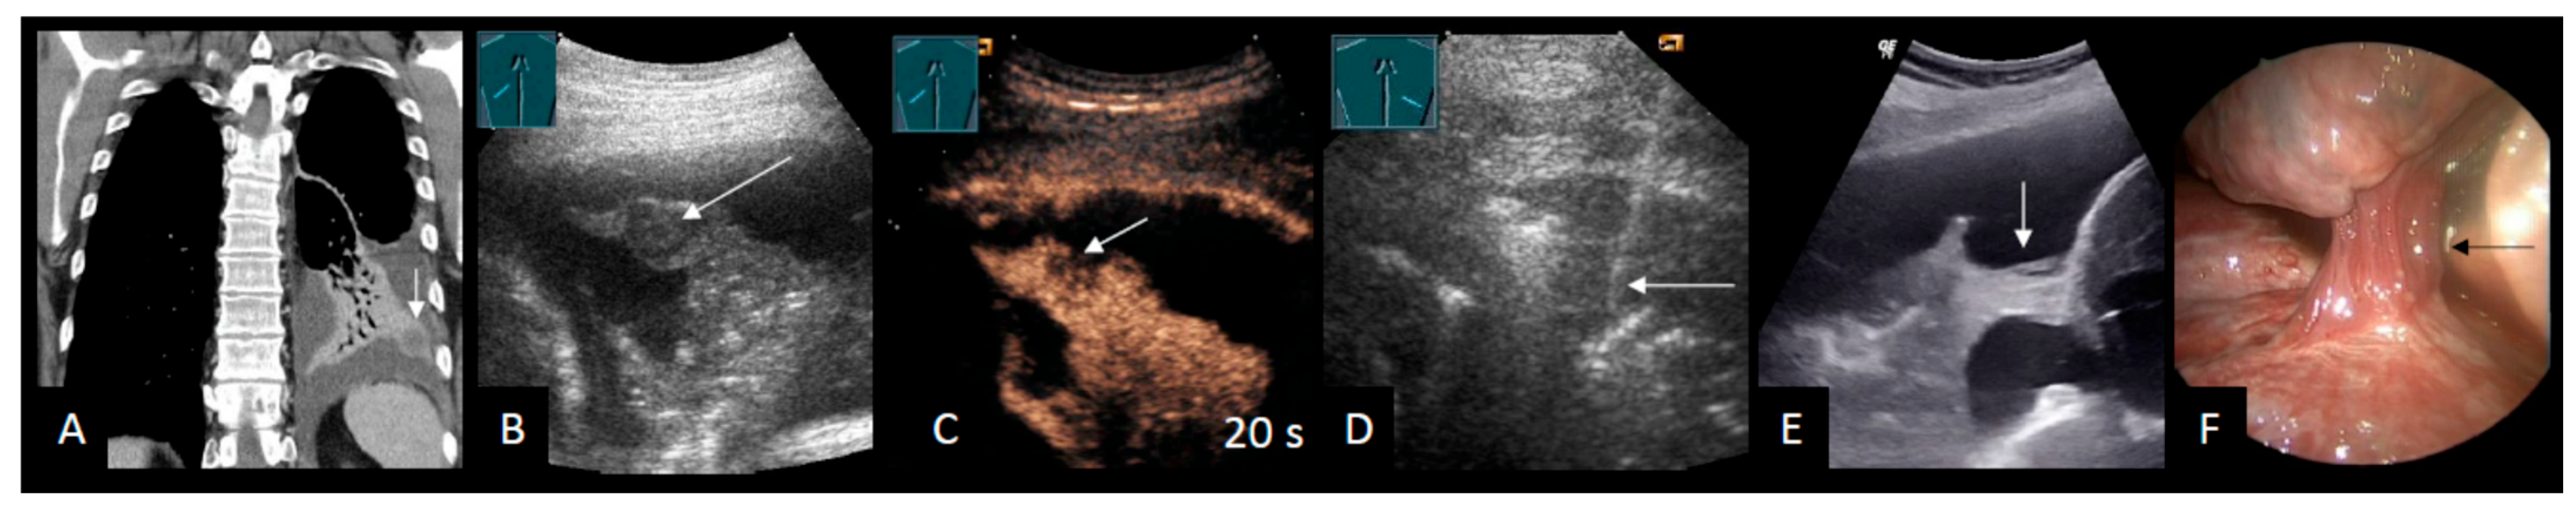

2.3. Pleural Lesions

Additional Ultrasound Techniques

| CEUS | ||||

| Safai Zadeh et al. [53] | 2021 | n = 83, single-center, retrospective study | To evaluate the value of CEUS in differentiating malignant from benign PE | Sensitivity B-mode: 69.1% Specificity B-mode: 58.5% Sensitivity CEUS: 73.8% Specificity CEUS: 70.7% Subgroup (cytological negative, high risk for MPE): Sensitivity CEUS: 92.3% Specificity CEUS: 90.0% |

| Findeisen et al. [56] | 2022 | n = 63, single-center, retrospective study | To describe the value of CEUS for the differentiation of malignant from benign parietal pleural lesions (Pleural effusion in 50.8%) | Sensitivity CEUS: 92% Specificity CEUS: 54% |

| Yang et al. [58] | 2022 | n = 50, single-center, prospective study | To investigate the diagnostic capabilities of B-mode LUS and CEUS in terms of differentiating between benign and malignant pleural diseases | Multivariate logistic regression: Sensitivity 93.3% Specificity 90.0% |